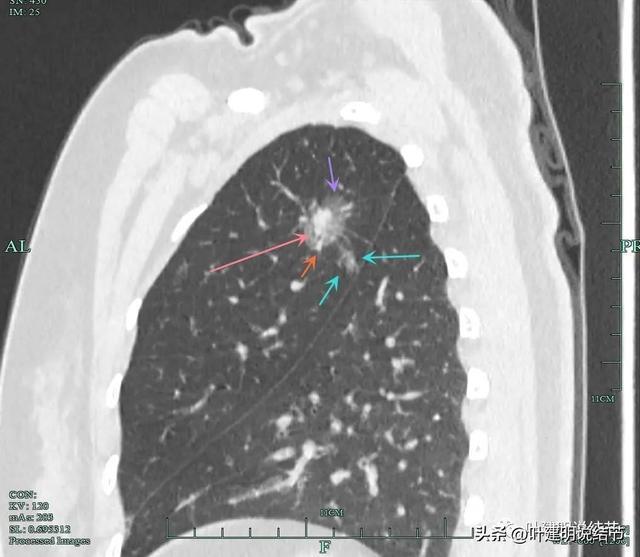

摘要:,,近日有報道稱,一位患者通過食用三七成功消除肺部結節(jié),這一自然療法展現(xiàn)出奇跡般的效果。這一療法為肺結節(jié)患者提供了新的選擇,展示了食療在疾病治療中的巨大潛力。患者應注意,每個人的身體狀況和結節(jié)情況不同,此方法不...